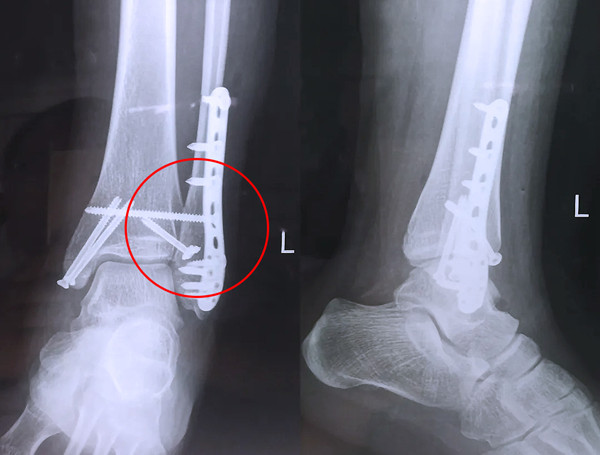

踝關節(jié)骨折在X影像上的表現(xiàn)有很多種。如內(nèi)踝骨折和外踝骨折,我們可以在影像上看到骨折處的骨折線是不連續(xù)的。還有后踝的骨折,內(nèi)踝、外踝、后踝聯(lián)合在一起發(fā)生的骨折,我們稱之為“三踝骨折”,這些都是在X影像上能夠顯示出來的。

三踝骨折